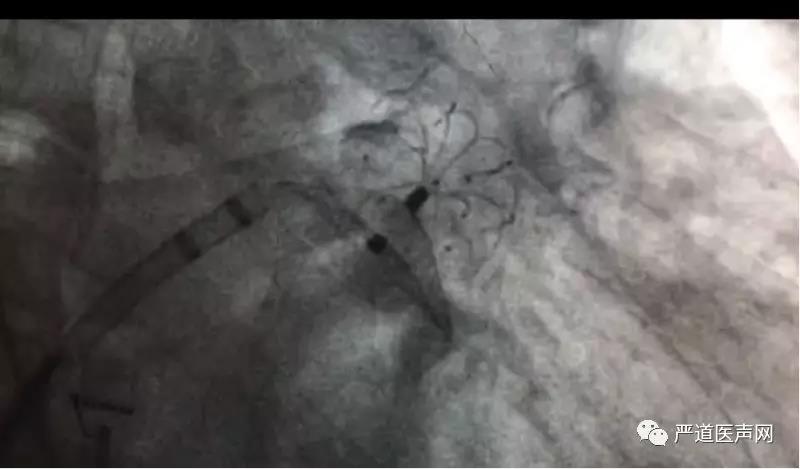

此次接受手术的是位71岁的男性患者,因反复胸痛10余年,心悸8年而入院寻求治疗,被诊断为心律失常持续性心房颤动,合并冠状动脉粥样硬化性心脏病,高血压病3级极高危组,陈旧性心肌梗死等其他病种,CHA2DS2-VASC=3,HAS-HLED=3,符合房颤消融及左心耳封堵适应症,循例对其施行房颤消融联合左心耳封堵手术。当日,在射频消融双侧肺静脉隔离完成后,置入猪尾导管进行左心耳造影,测量左心耳固定盘参考线为23.5mm,密封盘参考线为25.4mm,选用LAmbre™2632封堵器成功封堵,造影验证符合LAmbre™ COST释放原则后释放封堵器。释放后造影提示封堵完全,无残余分流;且在经食道超声0°,45°,90°,135°切面提示封堵完全,对二尖瓣及左上肺静脉结构功能无影响。

左心耳封堵效果